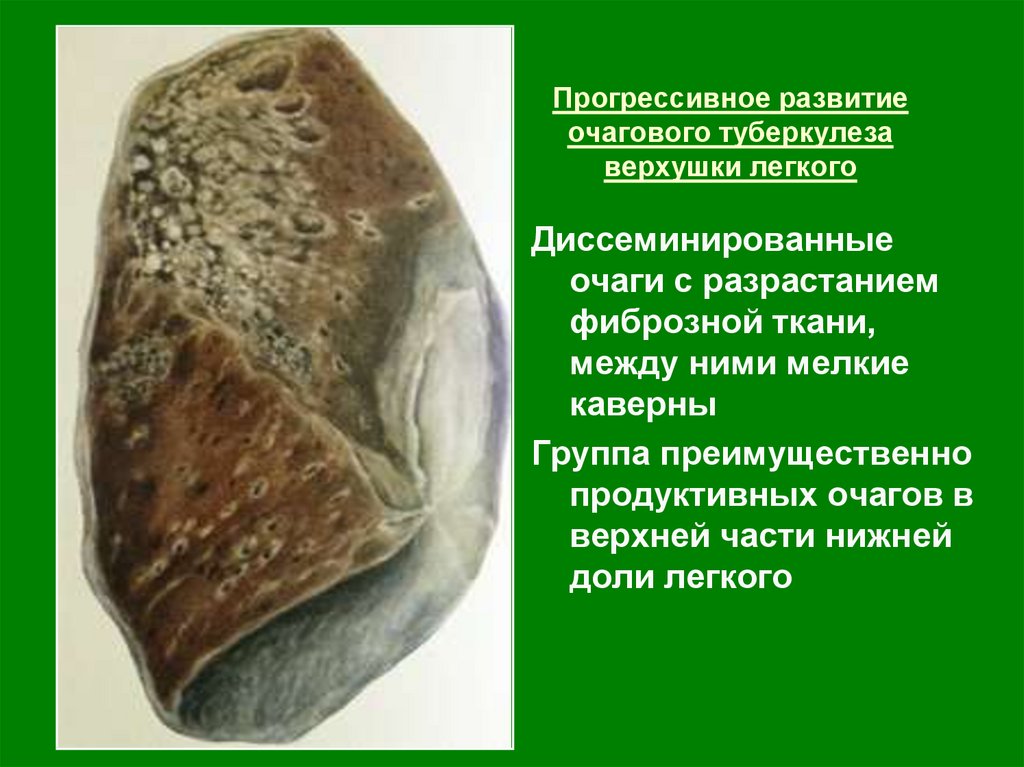

Очаговый и инфильтративный туберкулез презентация - 94 фото